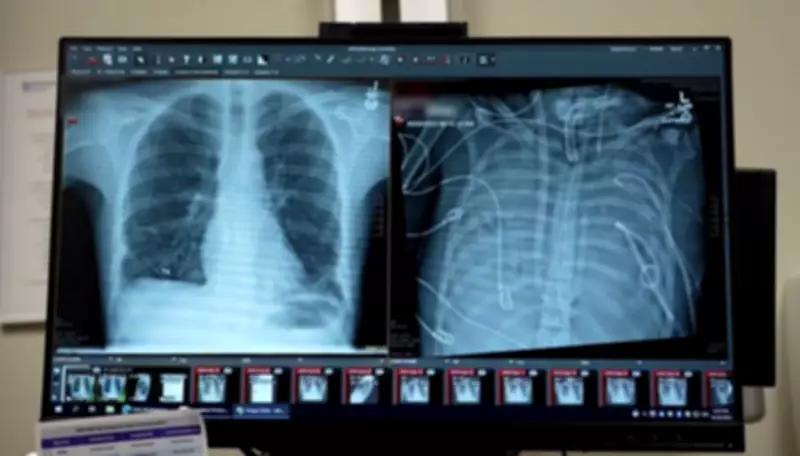

Uma equipe de cirurgiões nos Estados Unidos realizou um procedimento médico extraordinário que manteve um paciente vivo por mais de 48 horas sem pulmões. Após uma infecção grave causada por gripe, os médicos removeram os órgãos comprometidos e desenvolveram um sistema artificial para sustentar a vida do homem até que pudesse receber um transplante. O caso, publicado na revista científica Med, pode transformar radicalmente o tratamento de infecções pulmonares severas.

O paciente, um homem de 33 anos cuja identidade não foi revelada, desenvolveu uma infecção grave decorrente de uma gripe. O quadro evoluiu rapidamente para síndrome da angústia respiratória aguda (SARA), uma condição que provoca acúmulo de líquidos nos pulmões e reduz drasticamente os níveis de oxigênio no sangue.

Em pouco tempo, a função pulmonar entrou em colapso total, e outros órgãos vitais, como coração e rins, começaram a falhar. O estado dele era crítico. O coração parou assim que chegou ao hospital, exigindo reanimação cardiopulmonar imediata, conforme relatou o cirurgião torácico Ankit Bharat, autor principal do estudo.

Segundo o médico, quando a infecção é tão severa que o tecido pulmonar se deteriora extensivamente, os danos se tornam irreversíveis. É aí que os pacientes morrem, afirmou Bharat. Os pulmões estavam tão comprometidos que, além de não funcionarem mais, continuavam alimentando a infecção sistêmica, enquanto o organismo estava demasiado debilitado para receber imediatamente órgãos de um doador.

No caso específico, isso não era viável, pois os pulmões estavam agravando o quadro e deteriorando o organismo. Para resolver o impasse, os cirurgiões desenvolveram um sistema de pulmão artificial capaz de substituir temporariamente todas as funções pulmonares.

O resultado surpreendeu toda a equipe médica. Imediatamente após a remoção dos pulmões, o paciente começou a apresentar melhora significativa. A pressão arterial se estabilizou, outros órgãos passaram a funcionar melhor e a infecção cedeu consideravelmente.